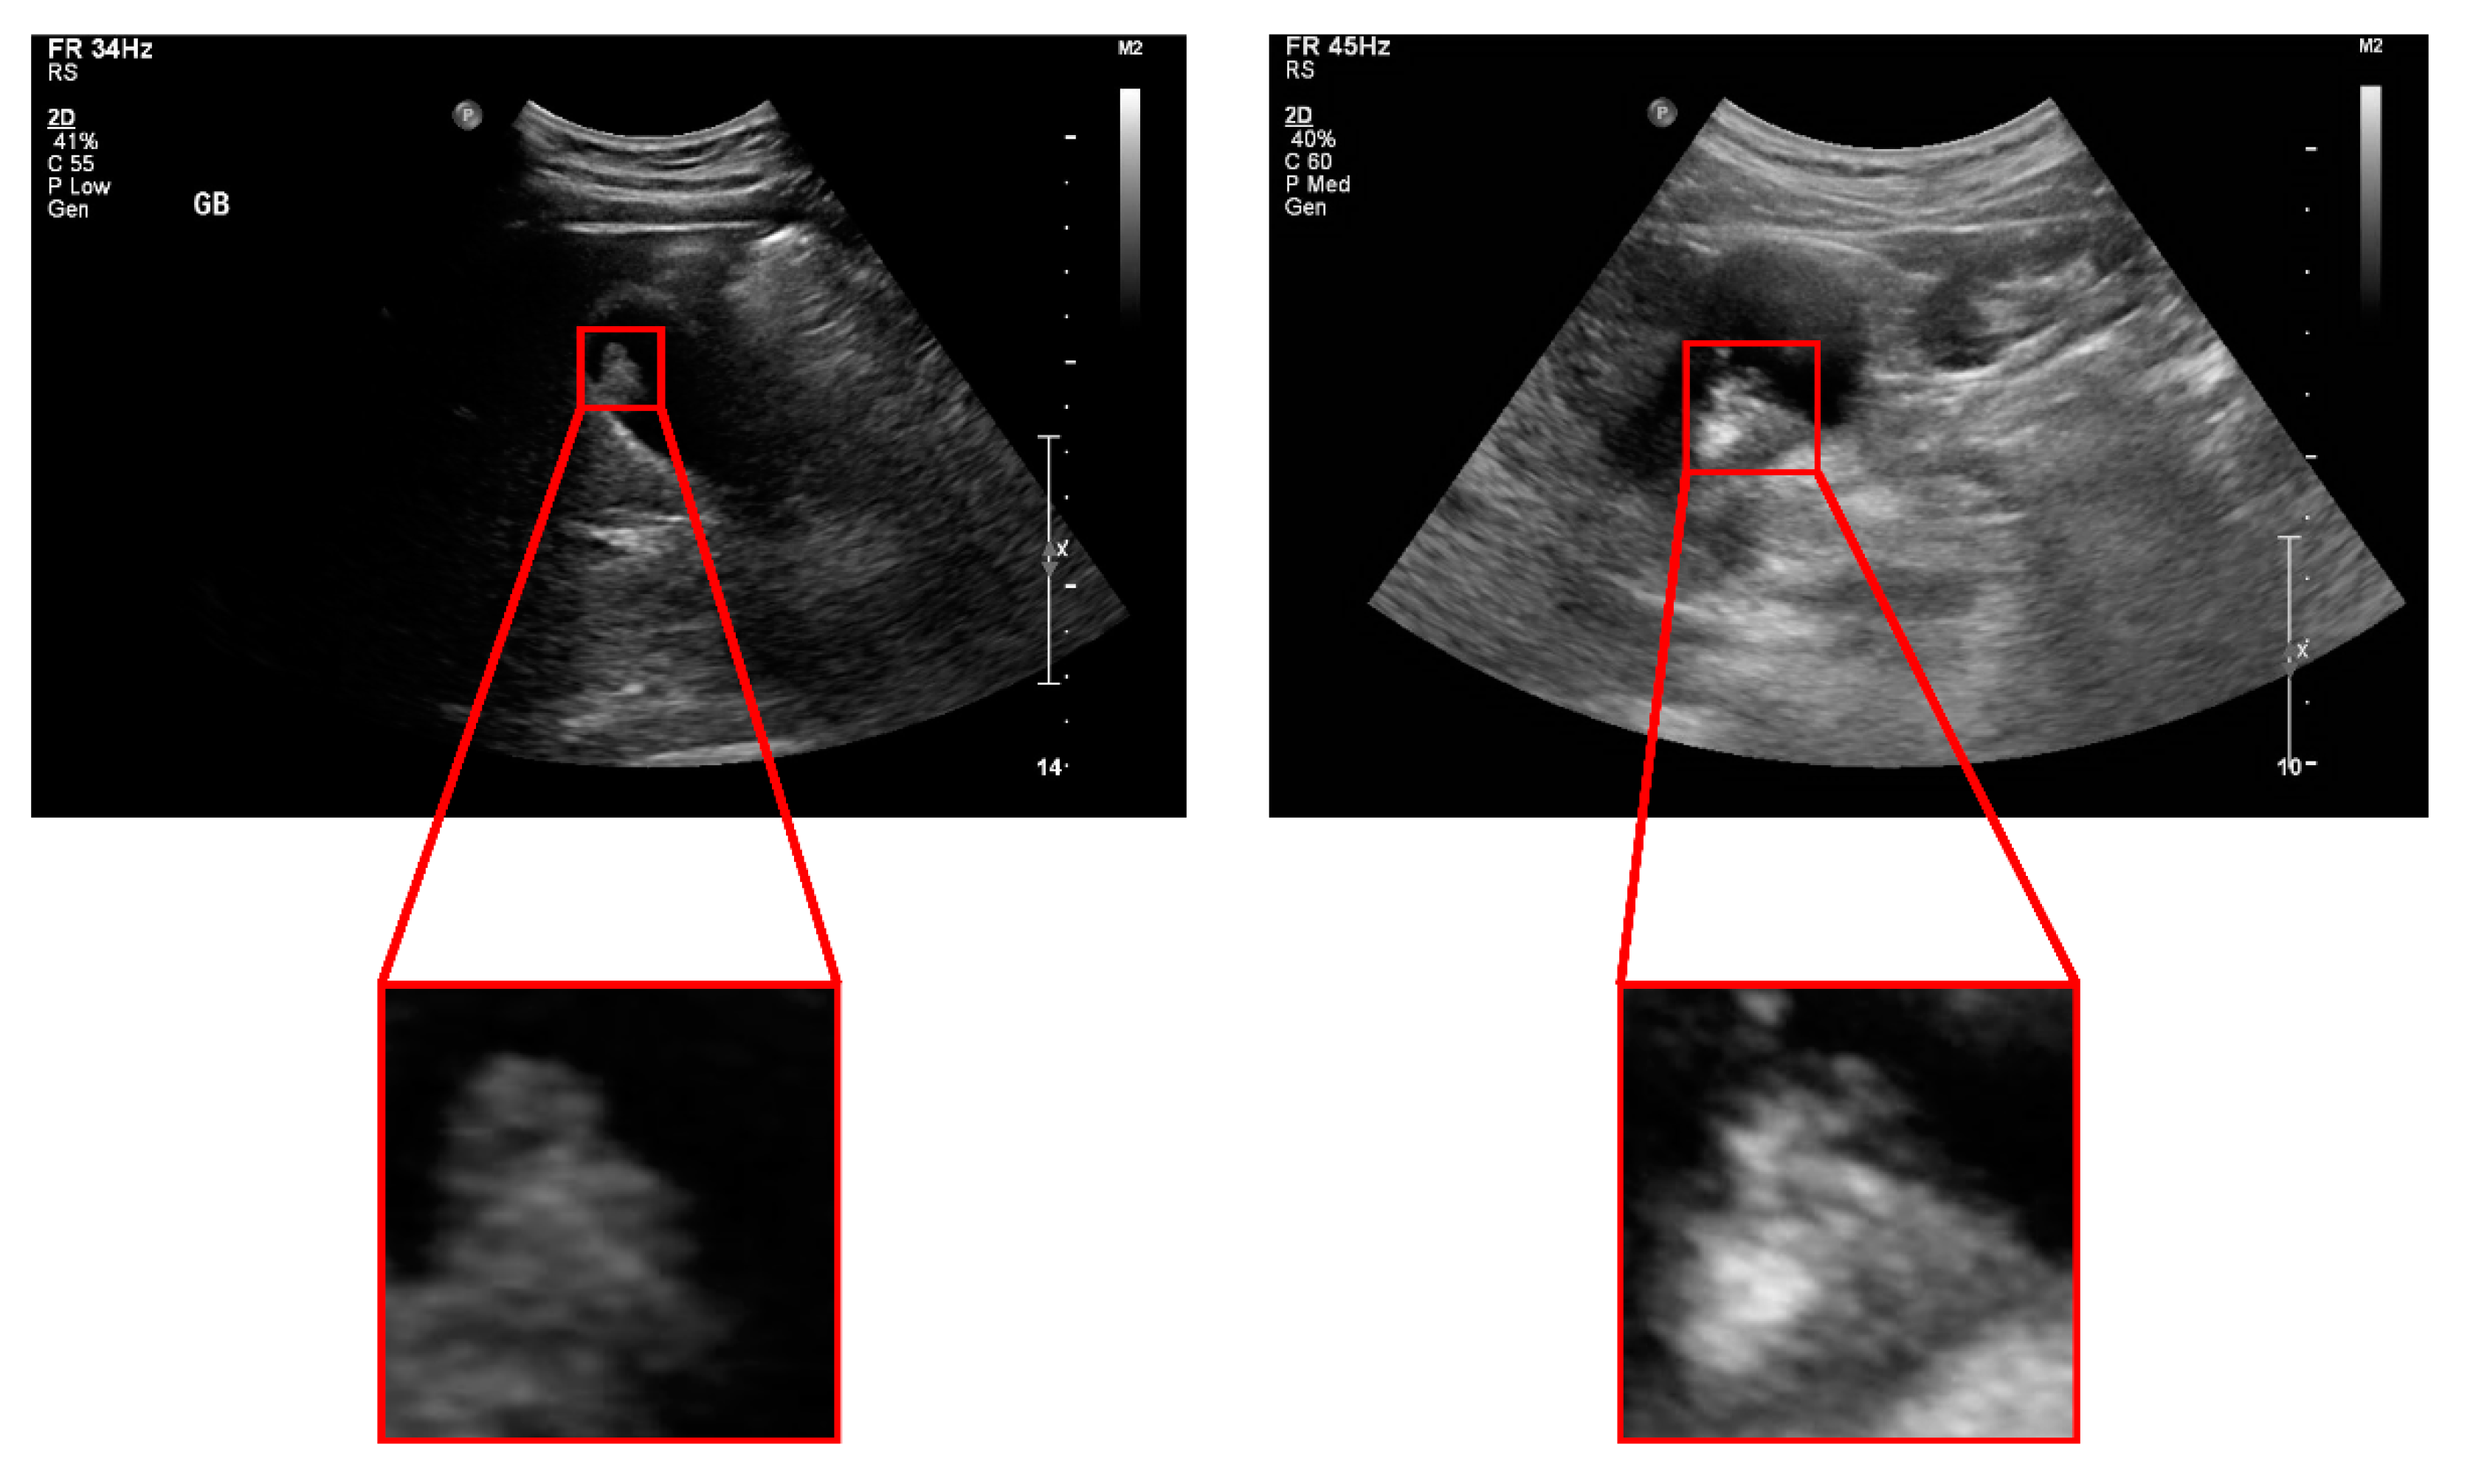

Gallbladder Polyp Classification in Ultrasound Images Using an Ensemble Convolutional Neural Network Model

2.1. Patients and Dataset Preparation